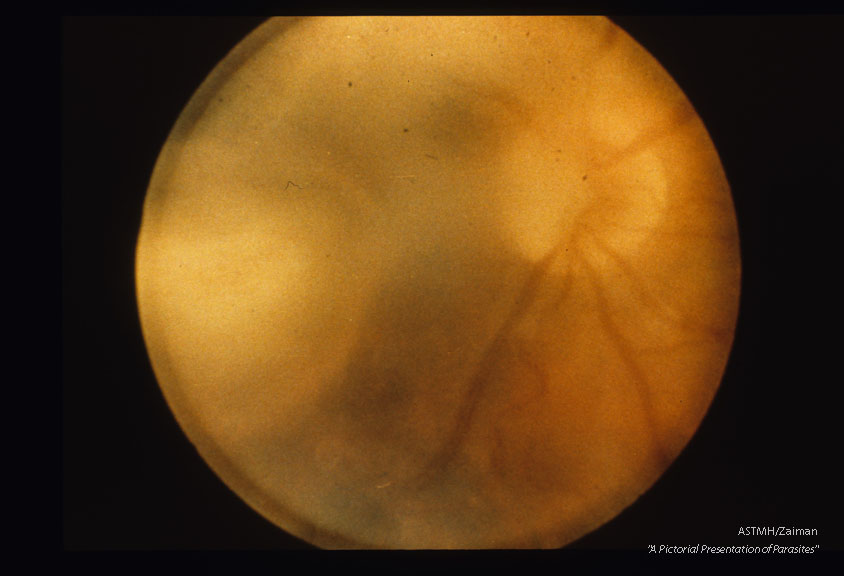

Acute retinal granuloma.

Toxoplasma gondii

Description: Acute retinal granuloma.